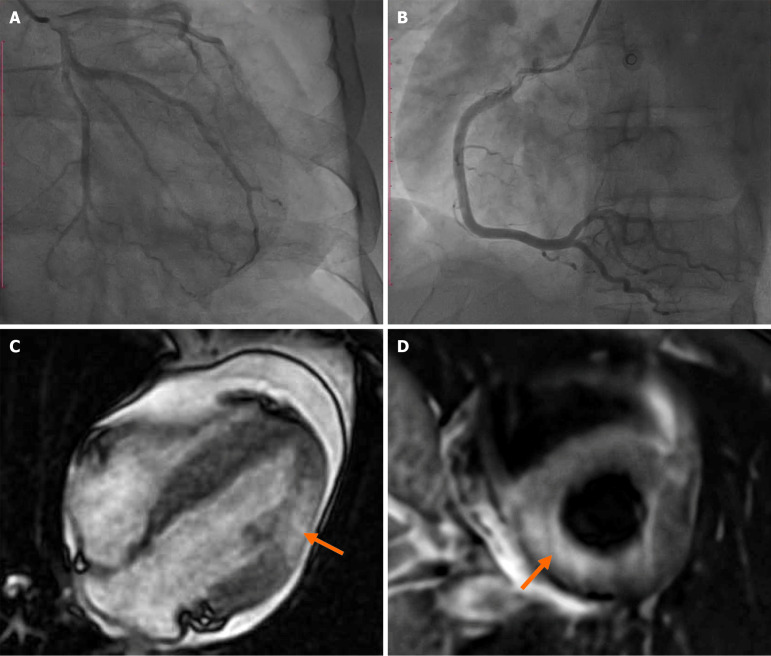

Eosinophilic myocarditis (EM) is a rare inflammatory condition of the heart, often associated with eosinophilic infiltration. While its causes range from allergies to autoimmune and infectious diseases, parasitic infections are an uncommon but critical etiology. This mini-review focuses on a case of EM in a 47-year-old male from Vietnam, linked to Schistosoma spp., Strongyloides stercoralis, and Toxocara spp. infections. The patient presented with severe chest pain and recovered fully after treatment with corticosteroids and albendazole. Drawing insights from this case and existing literature, we discuss the pathophysiology, diagnostic approaches, and therapeutic strategies for parasite-induced EM. Early diagnosis and tailored treatment are essential to improve clinical outcomes, especially in endemic parasitic areas.